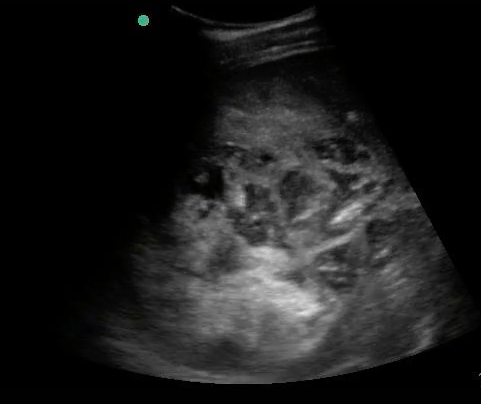

Figure 25. Large right lobar liver amoebic liver abscess. Note the complex heterogeneity and dirty shadowing.

Figure 26. A still image of the same right lobar liver amoebic abscess.

Figure 27. Transverse epigastric view of a separate left liver lobar amoebic abscess in the same patient.